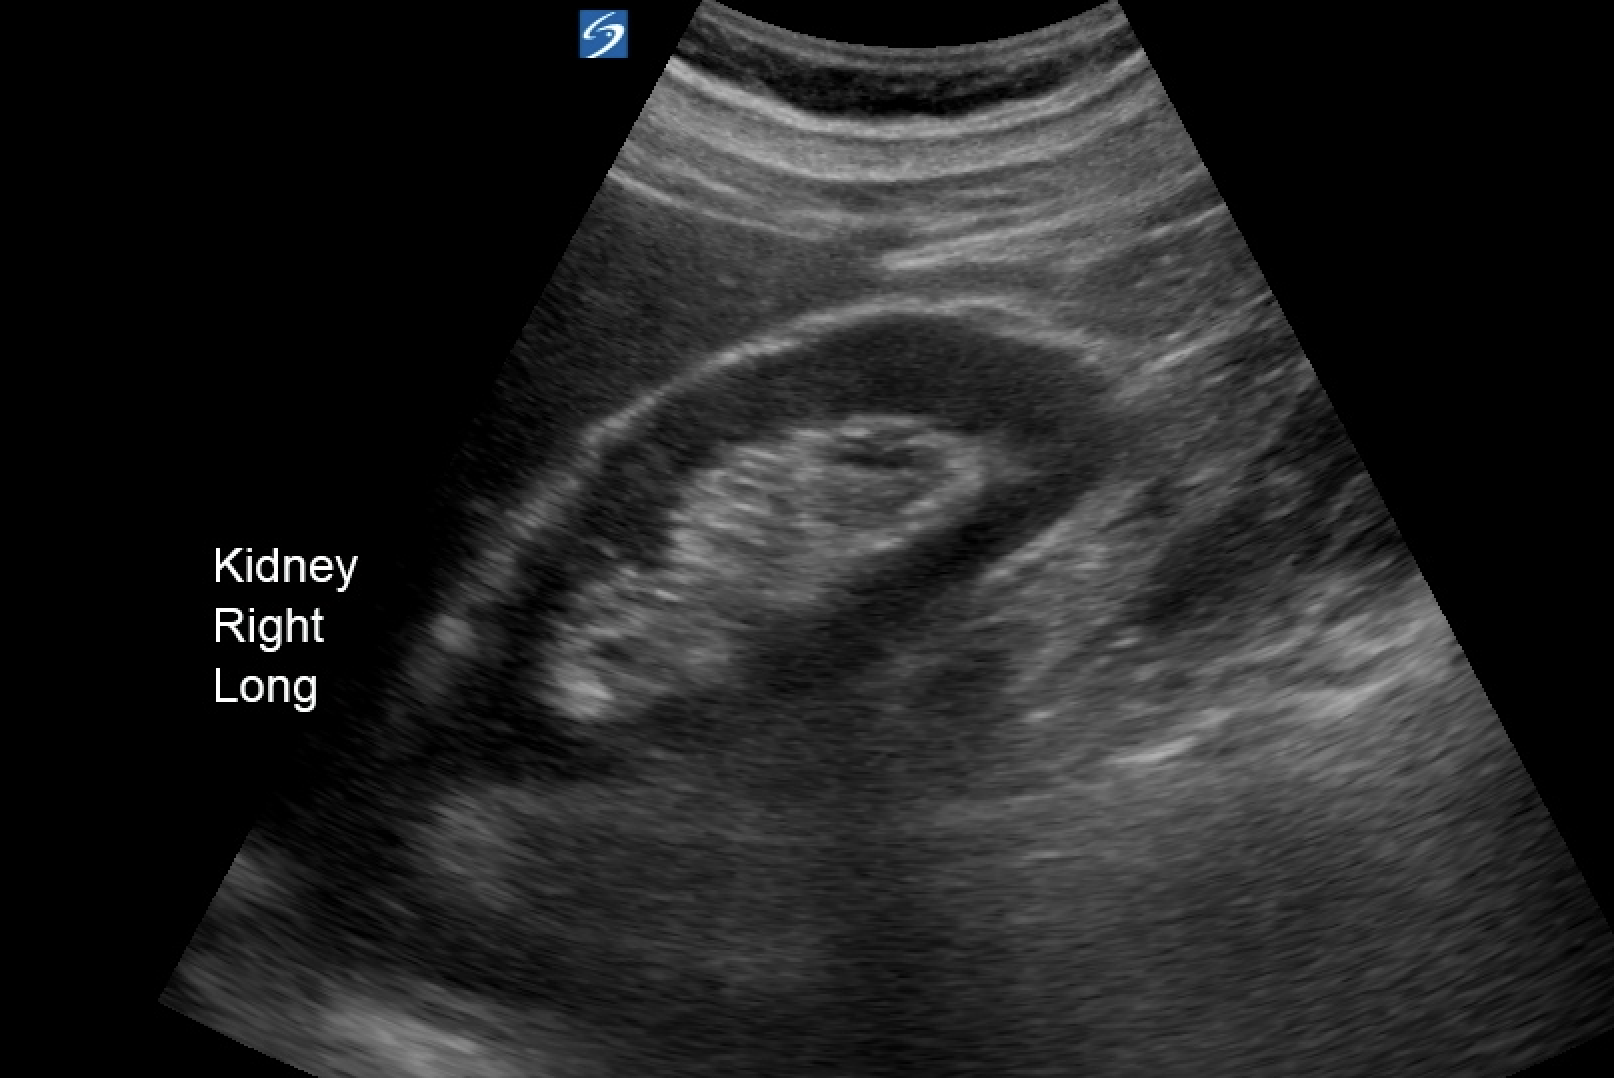

When looking at the kidney, each kidney should be 9-12cm long with a regular contour. The parenchyma typically is hypoechoic similar to normal liver. The bright white of gerota's fascia should be easily imaged.

Normal renal architecture and length

Gerota's fascia: hyperechoic line around the kidney

In the patient's scan, the upper pole of the R kidney, the parenchyma is hyperechoic and heterogenous. The upper pole is enlarged and the normally regular contour of Gerota's fascia is disrupted. It is difficult to see if there is anechoic free fluid in the cine loop. However on CT there is a fair bit of FF around the liver. This may have been visualised by imaging the paracolic gutter (location most sensitive for FF in trauma).